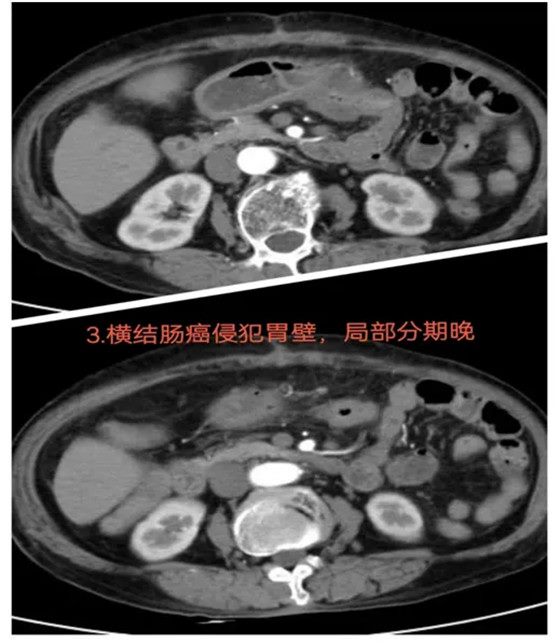

03结肠癌侵犯胃壁:迎难而上的手术抉择

患者4个月前因横结肠恶性肿瘤在外院接受手术治疗,但由于手术困难,原定手术被中止,仅行近端结肠造口术。随后,患者转入郑州大学五附院接受进一步治疗。经过多学科会诊及充分的术前准备,科室决定迎难而上,尝试再次进行手术切除。通过反复阅片和科内讨论,最终制定了详细的手术方案。术中探查发现,横结肠癌已侵犯胃壁,进一步增加了手术难度。最终,患者成功接受了经腹腔镜下横结肠癌根治术,并对受侵胃壁进行部分切除,同时进行了结肠造口还纳术。术后恢复良好。

难点总结:本病例的难点主要在于肿瘤侵犯了胃壁,导致手术范围和操作难度大大增加。虽然患者此前手术中止,但通过多学科评估和详细的术前准备,手术团队成功克服了这些挑战。

推荐理由:该病例展示了面对复杂肿瘤侵犯和手术难度增加的情况下,团队通过多学科协作和充分术前准备,成功完成了高难度手术。特别是在肿瘤侵犯胃壁的情况下,手术方案的精确制定和腹腔镜技术的应用确保了肿瘤的根治性切除,并有效进行了结肠造口还纳术。术后患者恢复顺利,腹部症状明显减轻,体现了精准治疗和细致术前评估的重要性,为类似病例提供了宝贵经验。